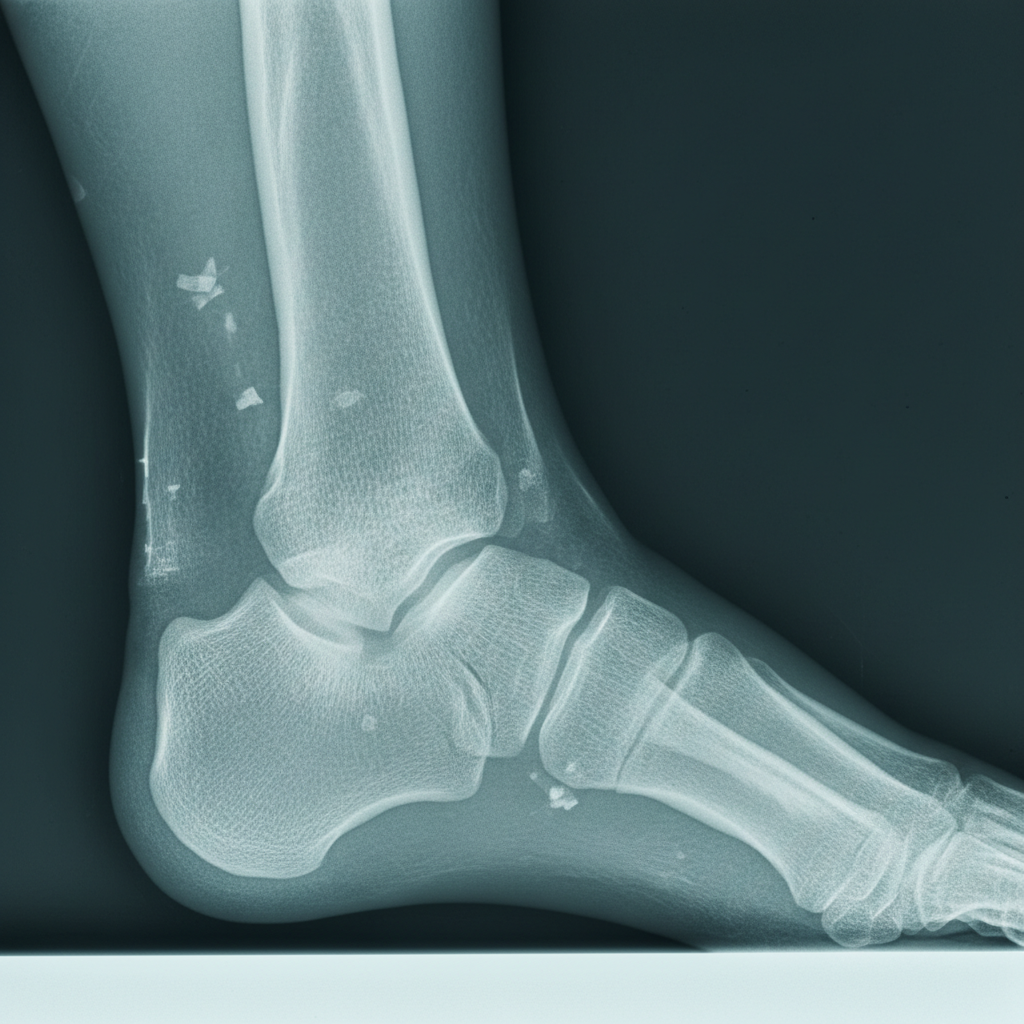

골절 진단서부터 수술 기록지, 입퇴원 기록, 외래 진료 기록, 처방전, 영상 자료(X-ray, MRI 등)까지 모든 의료 기록은 빠짐없이 보관해야 합니다. 이 모든 기록이 외측복사골절 후유장해를 증명하는 핵심적인 증거가 되기 때문이에요. 혹시 모를 상황에 대비해서 사본을 여러 개 만들어두는 것도 좋은 방법이에요. - 전문가와 반드시 상담하세요.